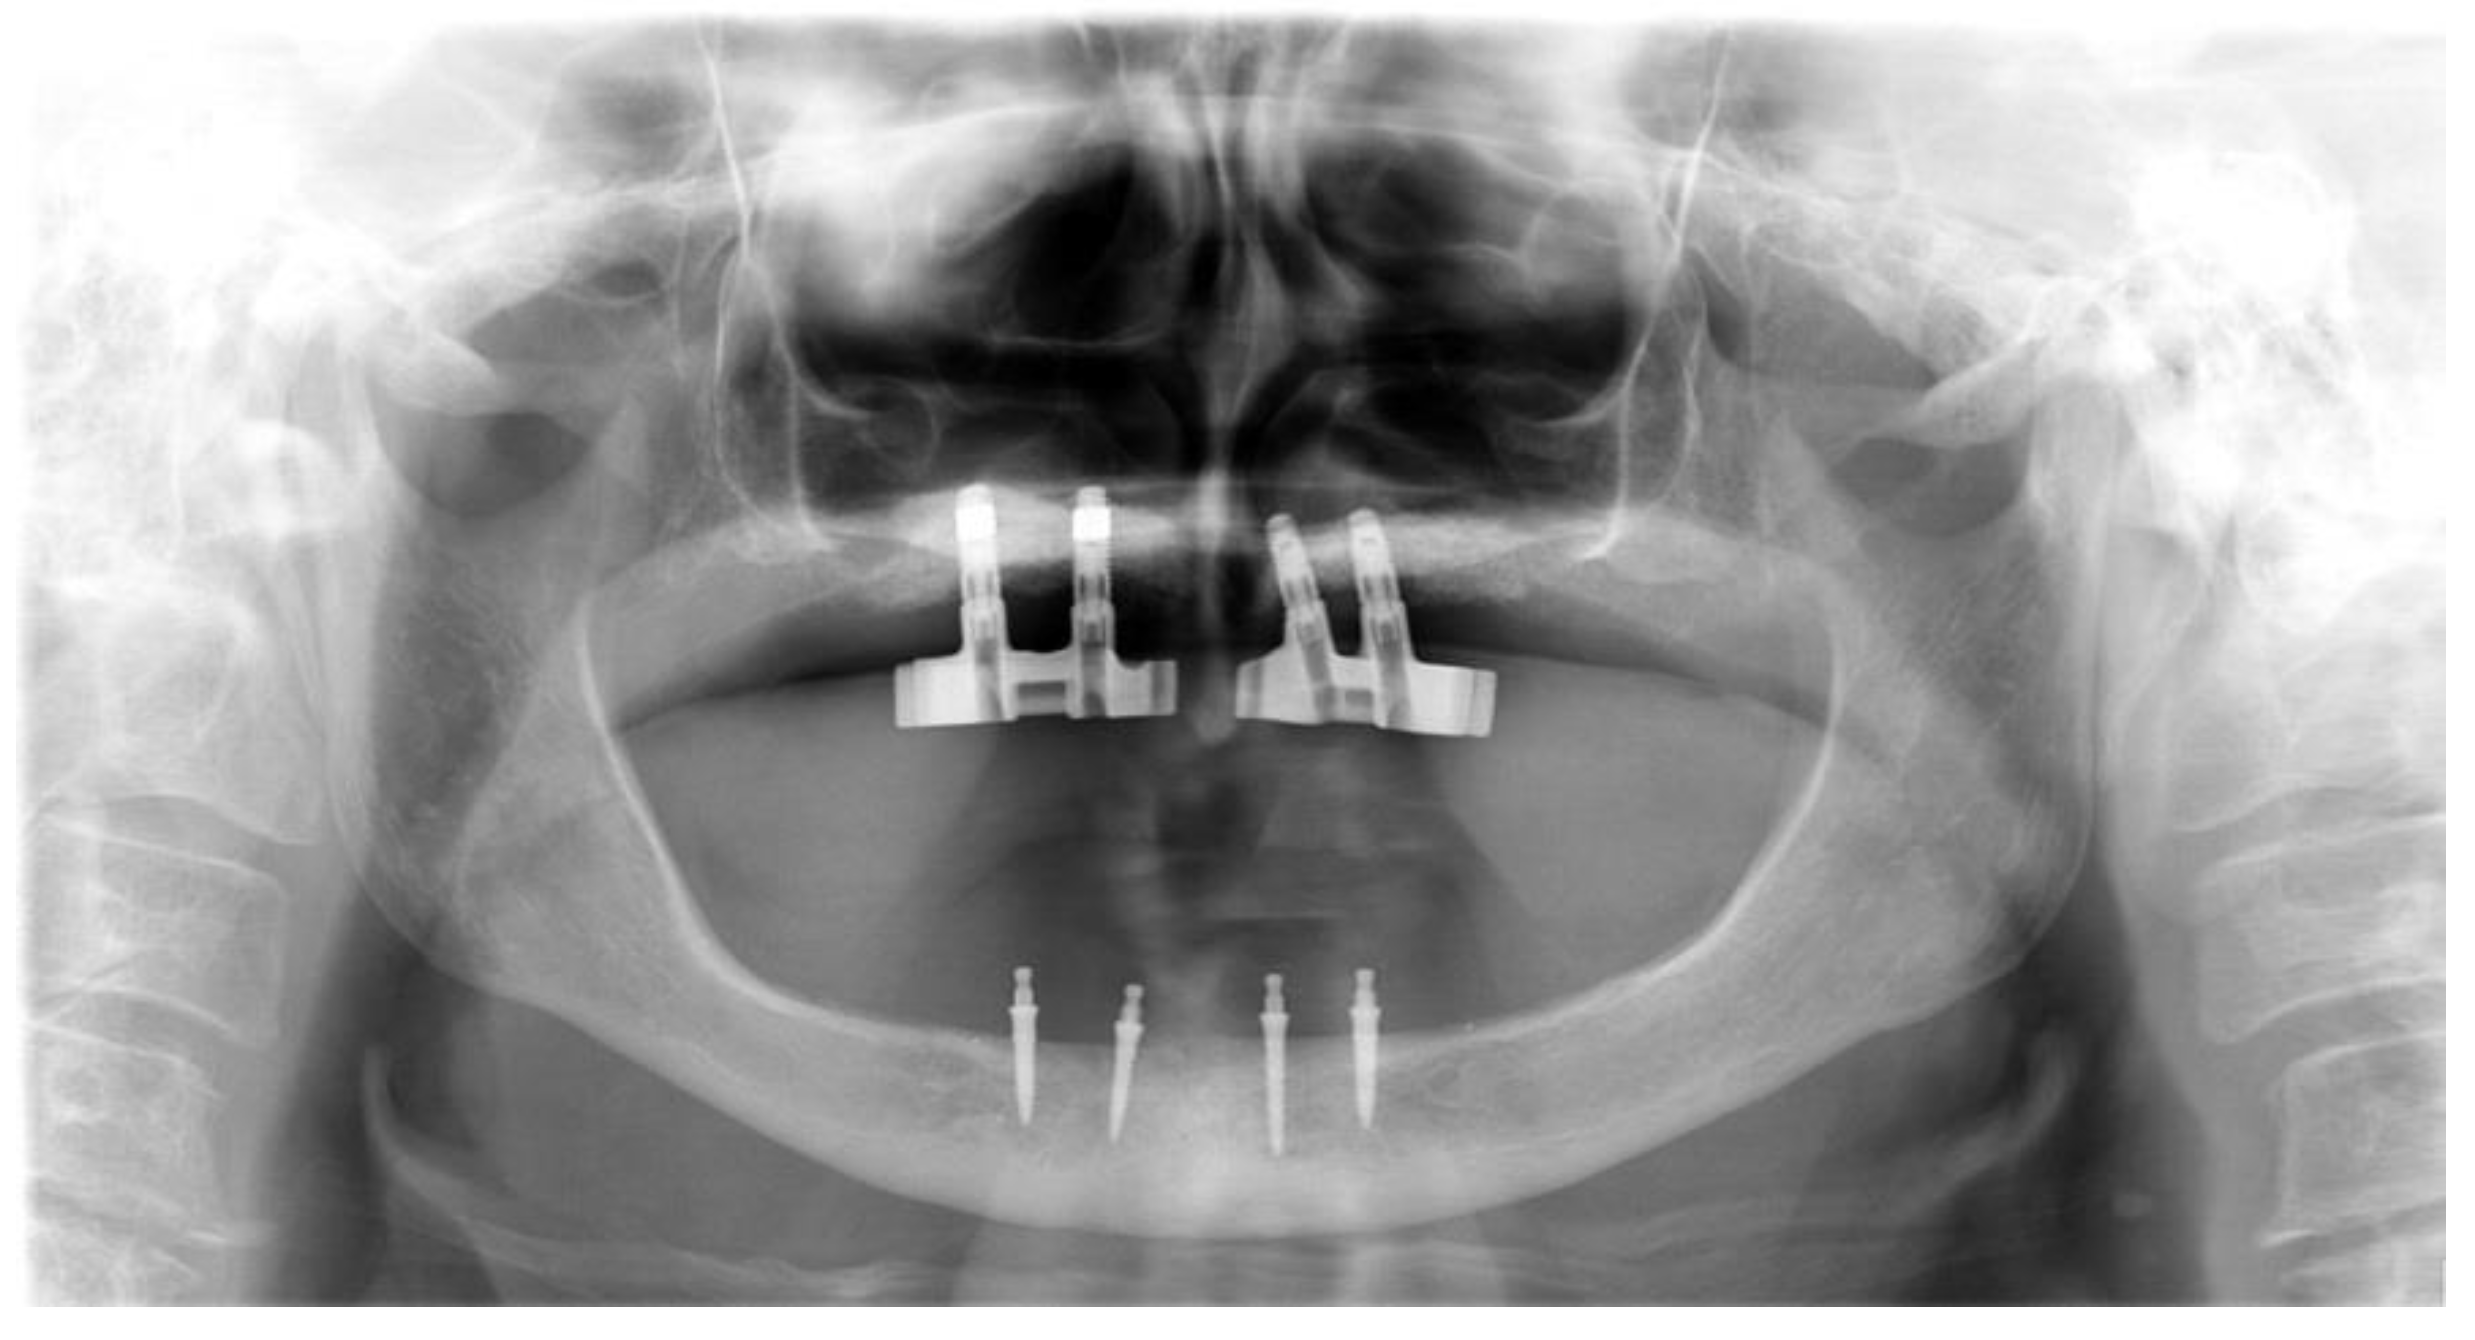

2. Case Report